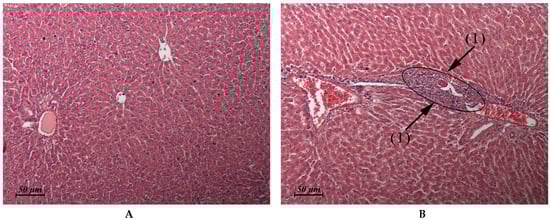

| Liver (Control: Figure 2A) | Similar to control | Micronecrotic foci in the vicinity of single triads (Figure 2B) | Similar to control | Similar to control |